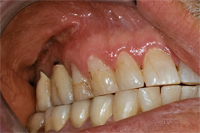

Ein 31 Jahre alter Patient zeigt einen starke Zahnfleisch-Rückgang im Oberkiefer (Abb. 1 und 3) und wir beschliessen, diese Rezessionen zu behandeln.

Der Erfolg der Behandlung ist deutlich in den Abb. 2 und 4 zu sehen. Sehr augenfällig konnte die Situation um den Eckzahn im linken Oberkiefer verbessert werden (vergleiche dazu Abb. 3 vorher und Abb. 4 nachher).